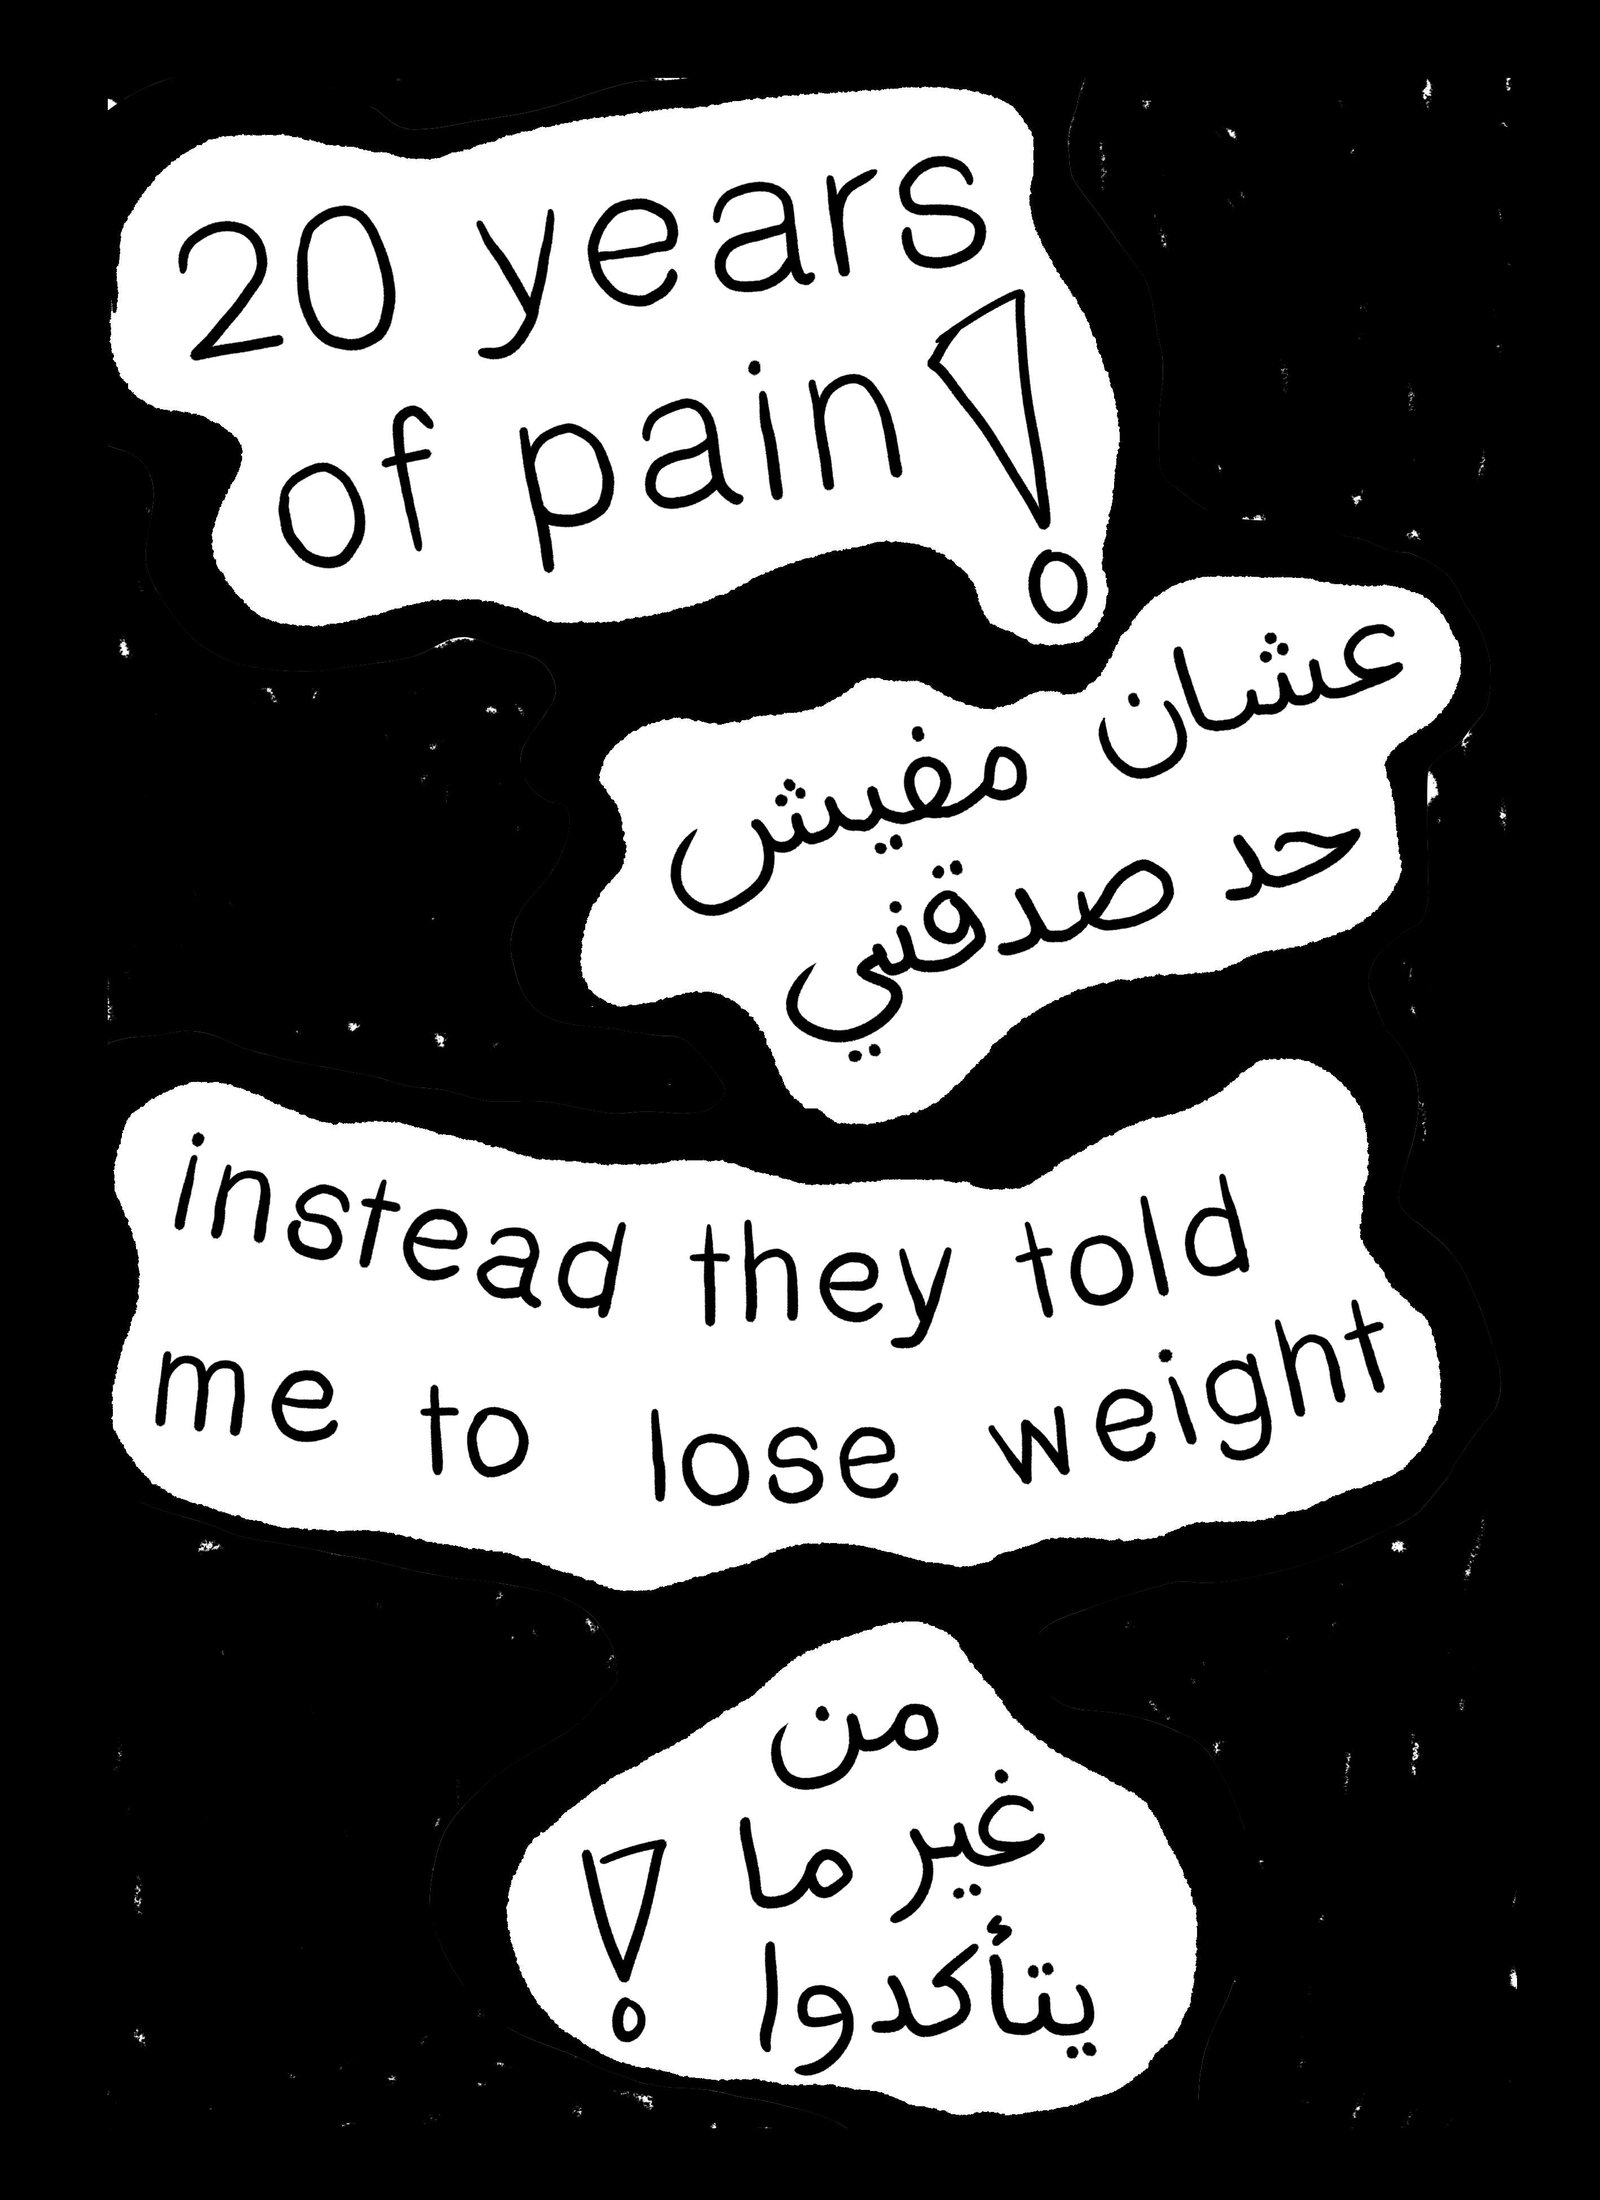

The P.O.V of the female patient, the reality of what is happening.

We believe you